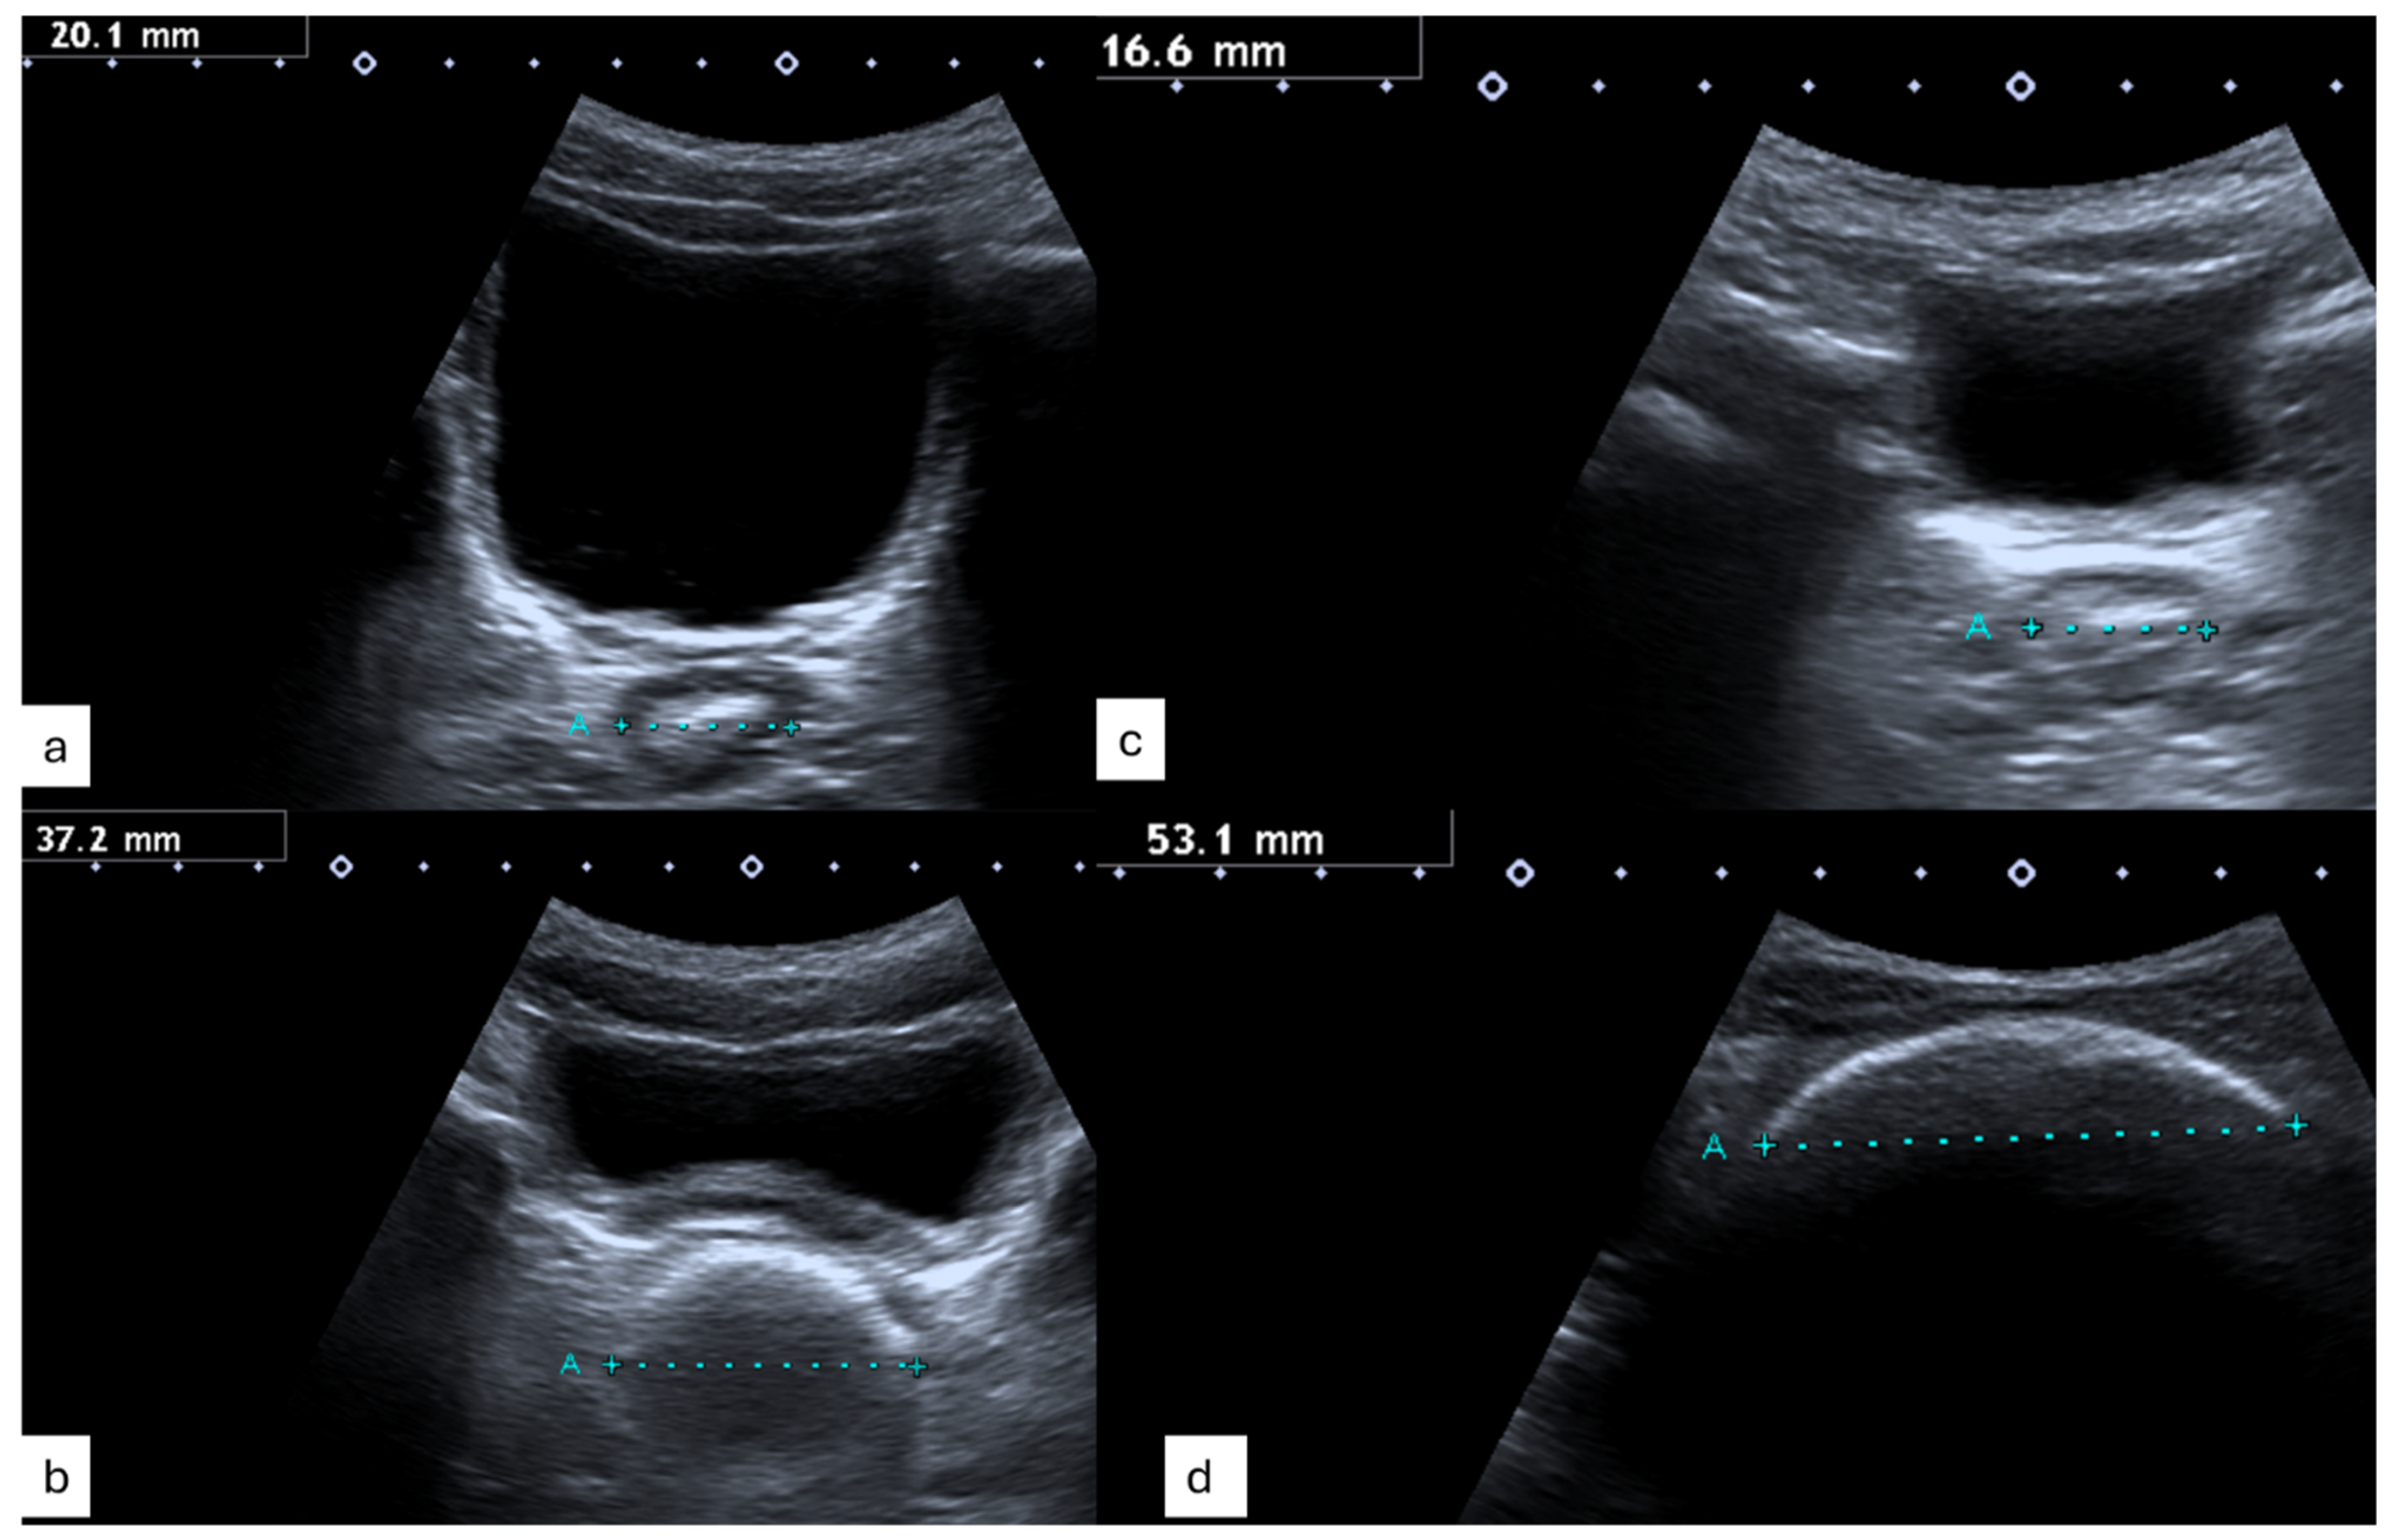

Figure 3 displays typical ultrasound images with a normal TRD (Figure 3a,c) and feacal load (Figure 3b,d) in children with Hirschsprung Disease (Figure 3a,b), healthy controls (Figure 3c) and those with functional constipation (Figure 3d).

Figure 3. Transrectal Diameter and Picture Constipation of (a) a child with HD and normal bowel function, (b) a child with HD and obstructive symptoms, (c) a healthy control and (d) a child with functional constipation and symptoms.